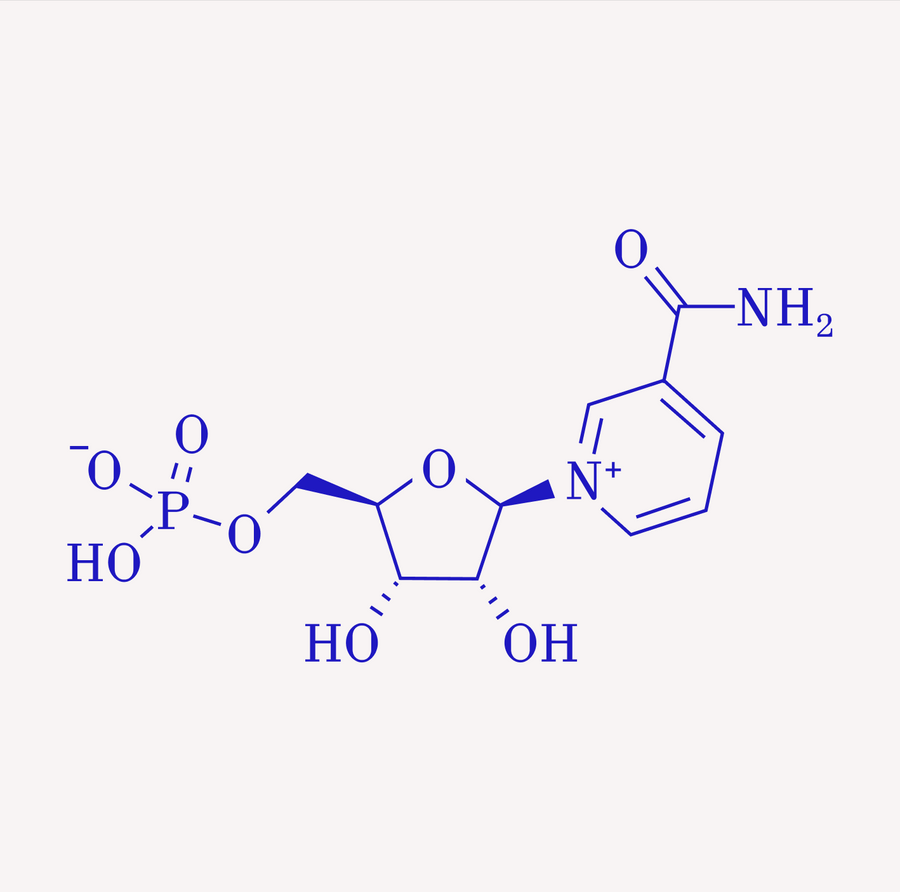

NMN

Boosts NAD⁺, supporting mitochondrial energy and DNA repair.

Alegre GFS, Pastore GM. NAD+-Vorläufer Nicotinamidmononukleotid (NMN) und Nicotinamidribosid (NR): Möglicher Beitrag der Ernährung zur Gesundheit. Curr Nutr Rep. 2023 Sep;

Mills KF, Yoshida S, Stein LR, Grozio A, Kubota S, Sasaki Y, Redpath P, Migaud ME, Apte RS, Uchida K, Yoshino J, Imai SI. Langfristige Verabreichung von Nicotinamidmononukleotid mildert altersbedingten physiologischen Abbau bei Mäusen. Cell Metab. 13. Dezember 2016;

Morifuji M, Higashi S, Ebihara S, Nagata M. Die Einnahme von β-Nicotinamidmononukleotid erhöhte den NAD-Spiegel im Blut, hielt die Gehgeschwindigkeit aufrecht und verbesserte die Schlafqualität bei älteren Erwachsenen in einer doppelblinden, randomisierten, placebokontrollierten Studie. Geroscience. 2024 Okt;

Soma M, Lalam SK. Die Rolle von Nicotinamidmononukleotid (NMN) bei Anti-Aging, Langlebigkeit und sein Potenzial zur Behandlung chronischer Erkrankungen. Mol Biol Rep. 2022 Okt;

Zhan R, Meng X, Tian D, Xu J, Cui H, Yang J, Xu Y, Shi M, Xue J, Yu W, Hu G, Li K, Ge X, Zhang Q, Zhao M, Du J, Guo S, Zhou B, Chui D, Chen YE, Sun Z, Dong E, Wang Y, Zheng L. NAD + rettet altersbedingte Schäden der Blut-Hirn-Schranke über die CX43-PARP1-Achse. Neuron. 15.11.2023;

Wang E, Wang Y, Zhang Z, Jiang Y, Zhao C. Biologische Eigenschaften, Synthesewege und Anti-Aging-Mechanismen von Nicotinamidmononukleotid (NMN): Forschungsfortschritt und Herausforderungen. Biogerontologie. 23. Juni 2025;

Han M, Hua JL. [Forschungsfortschritte zu Anti-Aging-Effekten von β-Nicotinamidmononukleotid (NMN)]. Sheng Li Xue Bao. 25. Dezember 2024;

Bonkowski und Sinclair. Gezielte Verlangsamung der Alterung: Der Aufstieg von NAD+ und Sirtuin-aktivierenden Verbindungen. Nature Reviews Molecular Cell Biology 2016

Rajman et al. Therapeutisches Potenzial von NAD-steigernden Molekülen: Der In-vivo-Beweis. Zellstoffwechsel 2018

Song Q, Zhou X, Xu K, Liu S, Zhu X, Yang J. Die Sicherheit und Anti-Aging-Wirkung von Nicotinamidmononukleotid in klinischen Studien am Menschen: ein Update. Adv Nutr. 2023 Nov;

Yi L, Maier AB, Tao R, Lin Z, Vaidya A, Pendse S, Thasma S, Andhalkar N, Avhad G, Kumbhar V. Die Wirksamkeit und Sicherheit einer Supplementierung mit β-Nicotinamidmononukleotid (NMN) bei gesunden Erwachsenen mittleren Alters: eine randomisierte, multizentrische, doppelblinde, placebokontrollierte, dosisabhängige klinische Studie mit Parallelgruppen. Geroscience. Februar 2023;